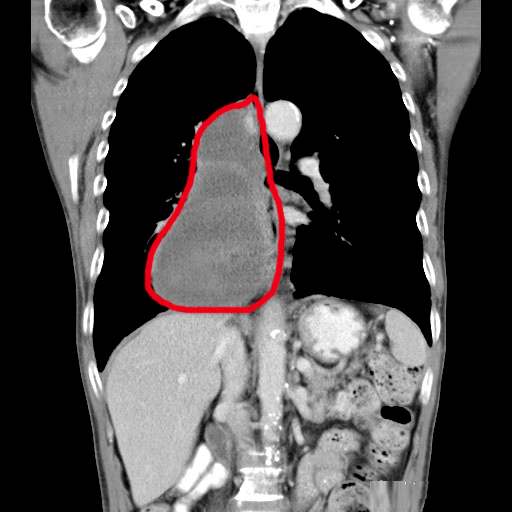

“介入化疗后,我父亲的肿瘤二十多厘米缩小到现在的十几厘米 。 ”张先生的女儿表示,父亲做介入治疗没有像其他化疗一样出现恶心、呕吐的副作用,而且第一个疗程结束后,回家休养了3天便能下地走路,呼吸也没问题了 。 对比第一次从东北来广州就诊,全程轮椅,咽不下饭,呼吸困难,现在的情况让她很满意 。